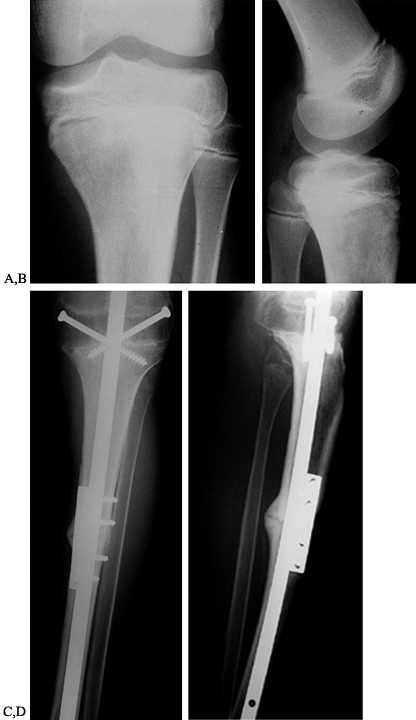

lateral radiographs. This gives the first clue as to the type of

neoplastic process occurring. A typical “conventional” osteosarcoma is

a medullary tumor that involves the metaphysis or epiphysis, or both,

of the lower end of the femur or upper end of the tibia. This tumor is

characterized by bone destruction and frequently is associated with

soft-tissue extension (Fig. 126.4). Variable

amounts of ossification are seen in osteosarcoma except for the

telangiectatic variant. Radiologic features such as “sunburst” or

Codman’s triangle, which is bone formation as a result of periosteal

elevation, can be seen on plain radiographs.

Figure 126.4. A: Anteroposterior (AP) radiograph of an 8-year-old girl with osteosarcoma of distal femur. B: Lateral radiograph of osteosarcoma. Note the bone destruction and periosteal reaction. C:

AP radiograph after resection of the distal femur. The knee is reconstructed with an expandable custom prosthesis. The articulation is a constrained condylar device. The expansion mechanism is at the top of the prosthesis. D: Lateral radiograph of an expandable knee prosthesis. |